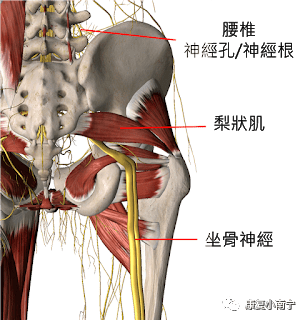

梨状肌卡压和腰椎间盘突出压迫坐骨神经痛的区别?

坐骨神经痛,屁股至腿部痛之梨状肌

坐骨神从梨状肌下缘通过出盆腔,因为梨状肌与坐骨神经的密切解剖关系